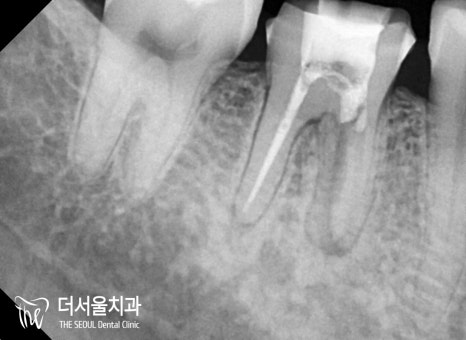

【 개선 후 모습 】

순차적으로 진료를 진행하여

감염된 곳을 깨끗하게 청소하고

밀폐, 소독, 충전을 진행했습니다.

재신경치료는 성공률이

매우 낮은 편에 속하기 때문에

의료진의 실력, 꼼꼼한 과정

모든 게 중요하다 할 수 있는데요.

놓치는 부분이 없도록

재차 확인을 거쳐

과정을 마칠 수 있었습니다.